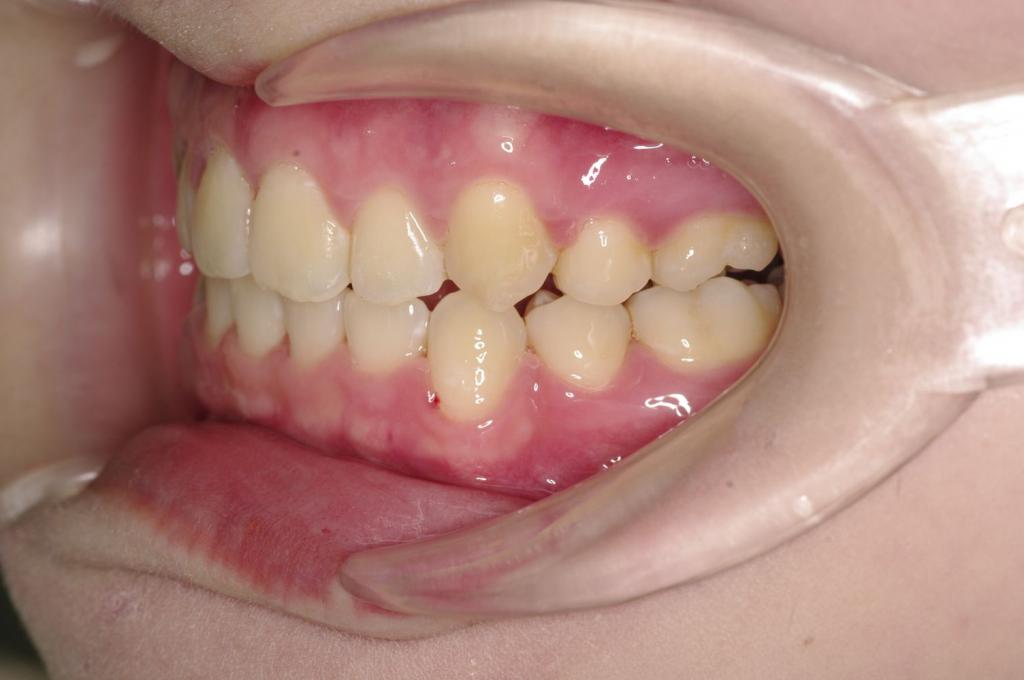

前歯、出っ歯・開咬の矯正治療

(治療期間、治療前後写真、治療方法、費用)WORKS